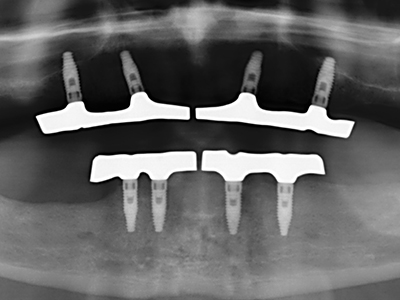

Fig. 11: El ortopantomograma posoperatorio presenta el aumento vertical y la elevación del suelo del seno.

Fig. 12: Después de seis meses de cicatrización se muestra una cresta maxilar vital con unas dimensiones suficientes en todas las direcciones.

Fig. 14: Incorporación de cuatro implantes RSX cónicos (Bego Implant Systems, Bremen).

Fig. 15: El control radiológico realizado al cabo de un año muestra una estabilidad del nivel óseo.

Fig. 16: También condiciones intraorales estables con incorporación de los implantes en la encía queratinizada.